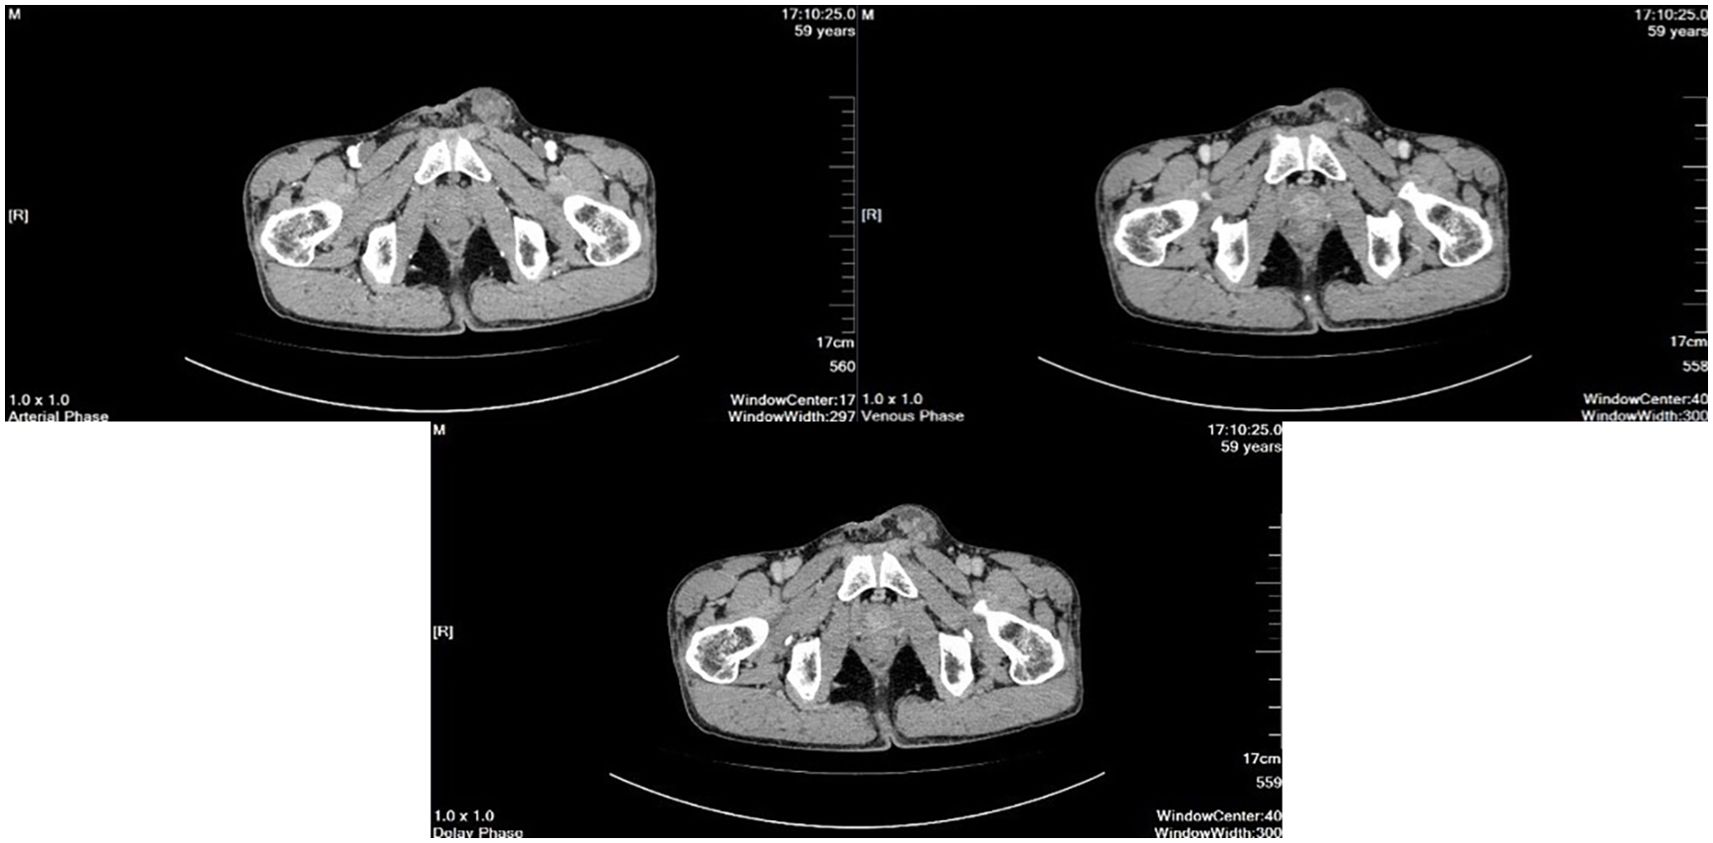

Scrotal ultrasound revealed that “the left testis was in the shape of ‘reverse C’, with abnormal morphology, the left epididymis had uneven echogenicity and rich blood supply, the left testis had an anterior liquid dark area, and the left spermatic cord was thickened, with uneven echogenicity and a slightly rich blood supply(Figure 1)”. The enhanced computed tomography (CT) scan revealed “cystic solid occupancy of the left testis: uneven density of the left testis, point-stripe enhancement in the parenchyma, showing a ‘fast-in-fast-out’ pattern, and no obvious enhancement in the cystic foci” (Figure 2).

Figure 2

Three cross-sectional CT scans of the pelvic region in arterial, venous, and delayed phases, demonstrating anatomical details. They have annotated measurements and settings on the sides.

Figure 2. The enhanced computed tomography (CT).